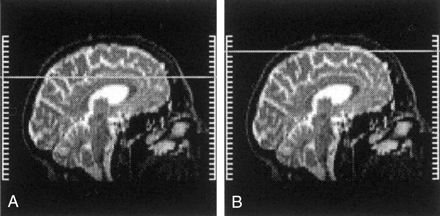

Brain MR imaging was performed with a 2.0-T magnet (Elscint; Haifa, Israel). Imaging sequences consisted of the following: 1) T1-weighted spin-echo sequence in the sagittal and axial planes (550/12 [TR/TE]) performed before and after the injection of gadolinium-based contrast material and 2) a long TR–dual-TE sequence in the axial and coronal planes (5 500/16, 128/1; 256 × 256 matrix; 24 × 24-cm field of view). The MR images covered the brain from the level of the foramen magnum to the high convexity of the scalp, and each examination resulted in the acquisition of 44 sections (3-mm section thickness, no gap) with each technique. Measurements were obtained on long-TR images (T2 weighted) of the high-convexity brain regions; these were defined as all axial sections above the upper border of the corpus callosum, depicted on the mid sagittal brain section (Fig 1). Contrast agent enhancement was used to exclude small enhancing lesions related to MS.

Midsagittal brain sections depict the anatomic level of the high-convexity images. VRSs were identified within these images.

A, Upper border of the corpus callosum.

B, Upper level of the brain.